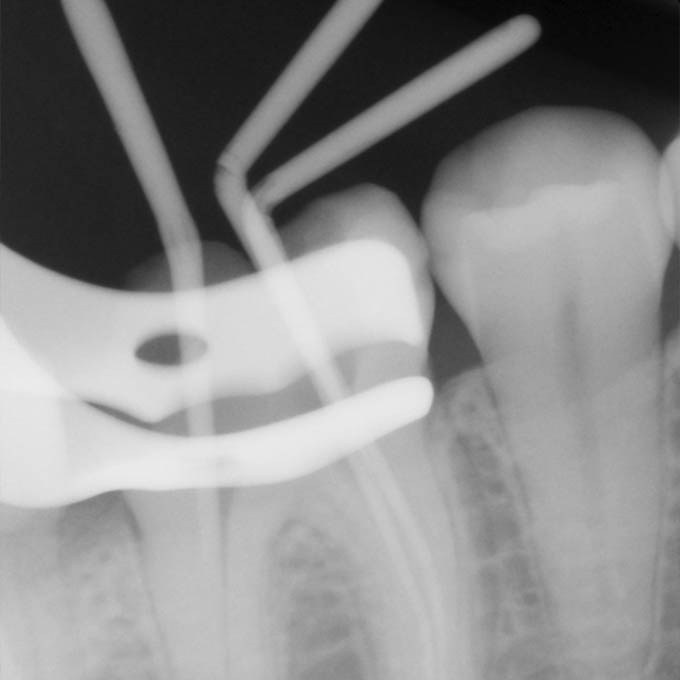

Зуб может иметь от 1 до 4 корневых каналов, а в редких случаях даже больше. Их диаметр зачастую не превышает 1 мм, поэтому увидеть какую-либо патологию и обеспечить ее эффективное устранение невооруженным глазом крайне сложно. Кроме этого, часто корневые каналы могут быть изогнутым, неровным, иметь ответвления, что еще больше усложняет задачу стоматолога. Микроскоп позволяет полностью решить эти проблемы.

Благодаря лечению под микроскопом наши врачи проводят обработку каналов с максимальной точностью, тем самым исключая риск повторного инфицирования зубных каналов и возникновения болей после лечения.

У микроскопа два плюса — многократное увеличение и мощная подсветка рабочего поля.

Это помогает врачу:

Увидеть скрытые детали: строение узких каналов зуба, трещины и микротрещины и др.

Бережно вылечить зуб. Врач отлично видит воспаленные ткани зуба и здоровые участки остаются нетронутыми.

Обнаружить и обработать труднопроходимые каналы. Зуб не придется перелечивать или даже удалять.

Качественно перелечить зуб после неудачного предыдущего лечения

Извлечь фрагменты обломанного инструмента в процессе лечения.

Спасти сильно разрушенный зуб от удаления.

Дентальный микроскоп — исключает риски ошибок

30-ти кратное оптическое увеличение в разы повышает точность диагностики и качество лечения корневых каналов.

Становится возможным определение скрытых каналов и ответвлений, трещин и перфораций корня.

Удаление только инфицированных тканей без повреждения здоровых.

Данный способ лечения каналов позволяет провести качественное равномерное трехмерное пломбирование даже сложных извилистых корневых каналов и микро-ответвлений горячей гуттаперчей без образования пустот.